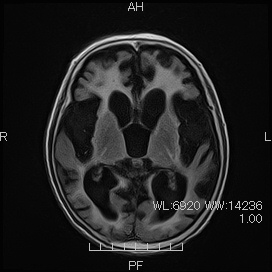

アルツハイマー型認知症の脳の様子

MRI画像

側脳室下角の開大と海馬の萎縮